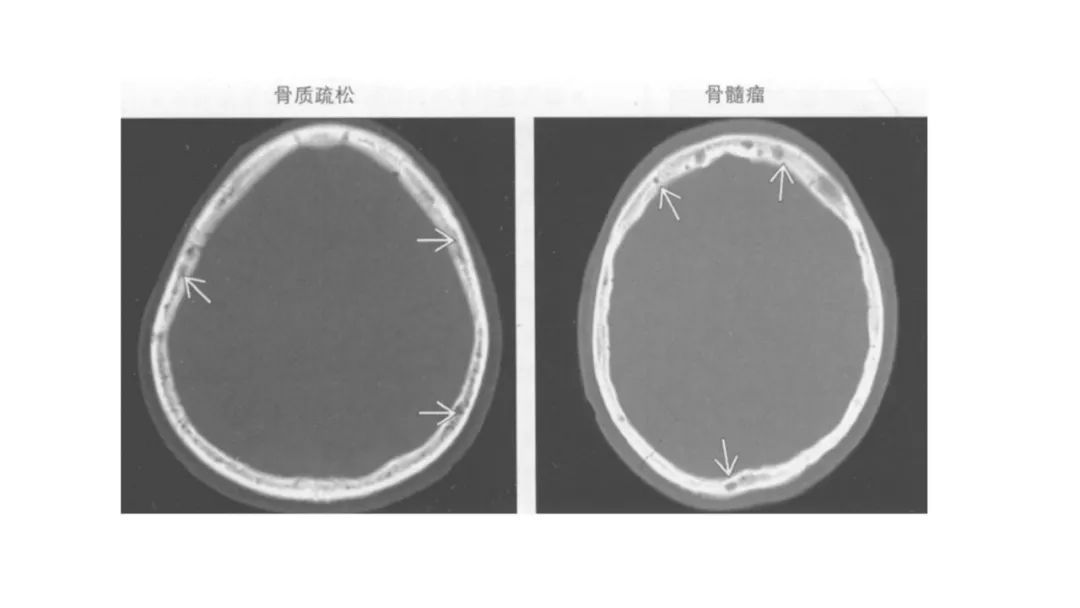

颅脑影像诊断基础知识讲座:颅骨病变